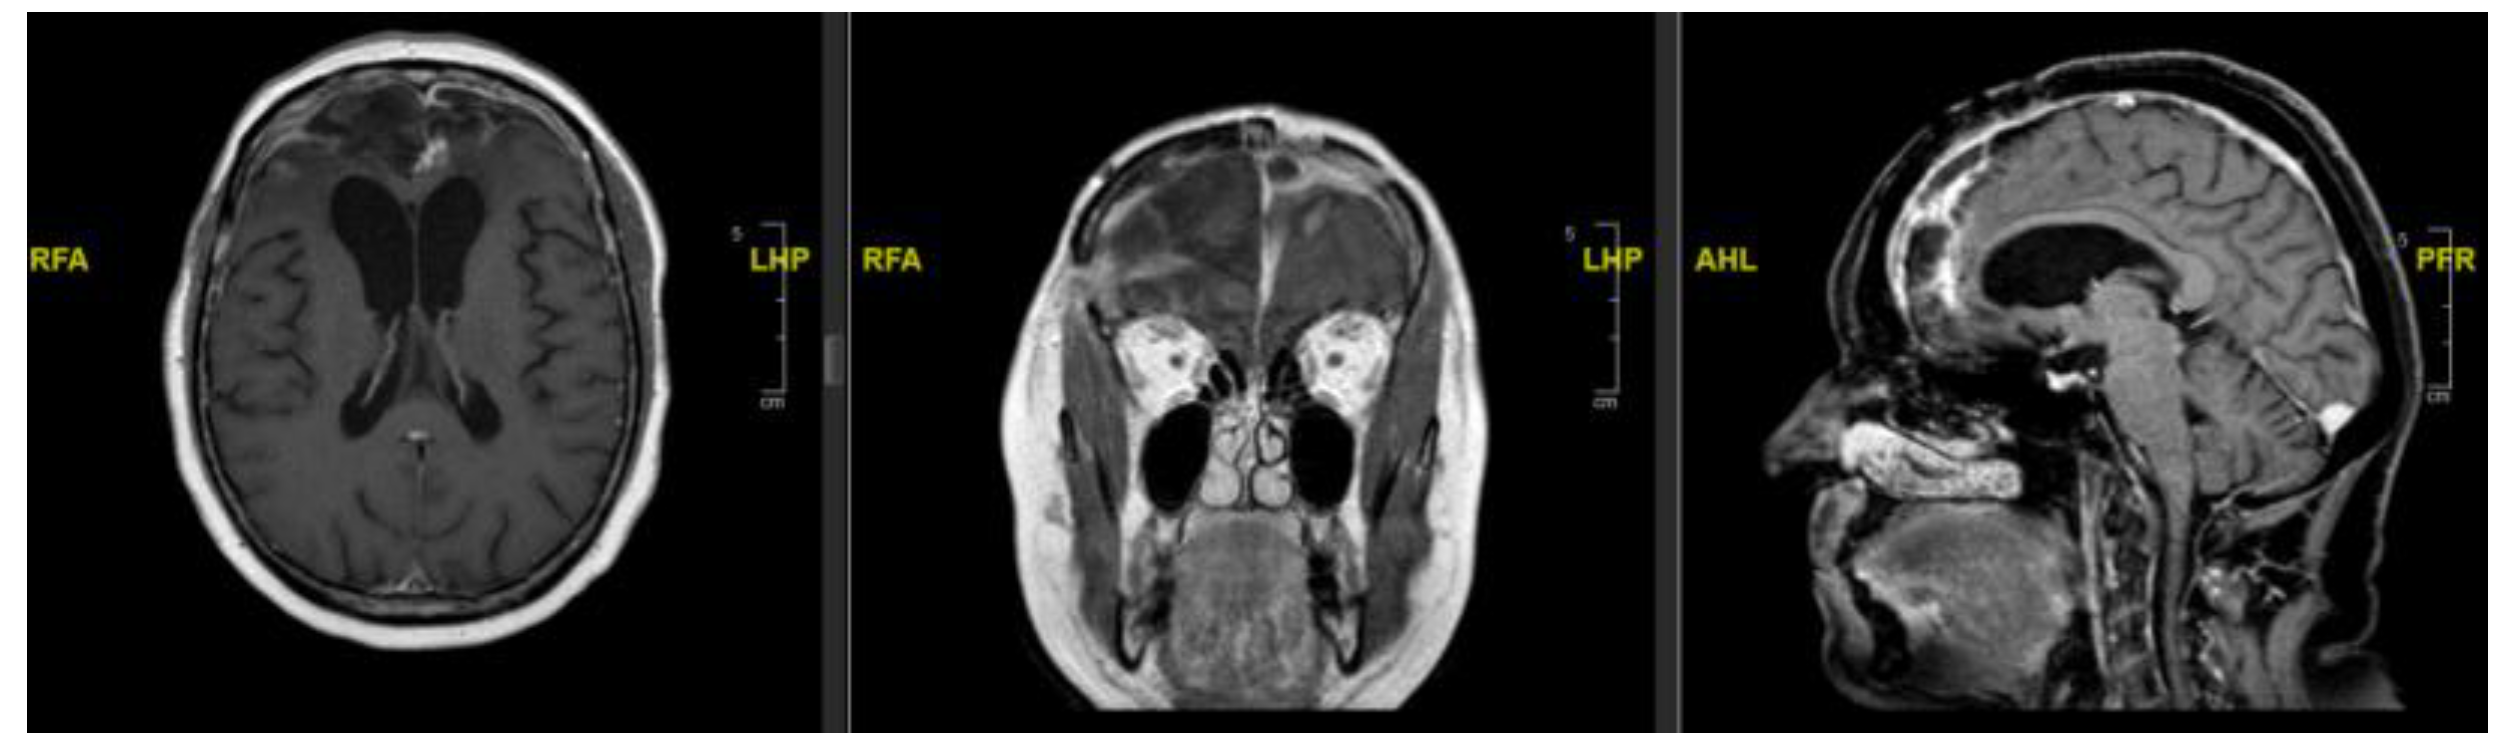

Background and Clinical Significance: Glioblastoma is the most common and aggressive primary malignant brain tumour in adults. Maximal safe surgical resection remains the cornerstone of treatment; however, tumour vascularisation may increase the risk of in-traoperative bleeding and complicate surgical management. Preoperative endovascular embolisation is commonly used for highly vascular intracranial tumours such as men-ingiomas, whereas its role in glioblastoma remains poorly defined. A focused literature review using the search string (((preoperative) AND (endovascular)) AND (embolization)) AND (glioblastoma) identified only two relevant publications, highlighting the scarcity of available evidence. In this context, we report a case series of three patients with intra-cranial lesions suspected to be high-grade gliomas who underwent preoperative angi-ographic evaluation and, when feasible, endovascular embolisation prior to surgical resection. Case Presentation: Three patients presenting with large intracranial lesions suggestive of high-grade glioma underwent preoperative digital subtraction angi-ography to assess tumour vascular supply (histological analysis confirmed the diagnosis of glioblastoma). In a 61-years-old woman with a right frontal tumour, selective catheteri-sation of a frontal branch of the right anterior cerebral artery enabled embolisation with coils, achieving partial tumour devascularisation before surgery. A second patient, a 53-year-old man with a large left temporo-fronto-insular mass extending to the corpus callosum, underwent embolisation of tumour feeders arising from the anterior choroidal artery using N-butyl cyanoacrylate and Lipiodol prior to resection. In a third case, a 77-year-old man with a left temporo-parietal lesion underwent preoperative angiography that demonstrated tumour capillary blush but no catheterisable feeding arteries, and embolisation was therefore not feasible. All patients subsequently underwent surgical resection without perioperative complications or new neurological deficits. Conclusions: Preoperative angiographic evaluation may help characterise tumour vascular supply in selected glioblastoma cases. When identifiable arterial feeders are present, endovascular embolisation may represent a feasible adjunct to facilitate surgical management. Further studies are required to better define the indications, safety profile, and potential benefits of this approach.